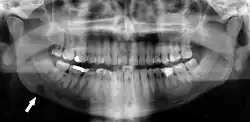

Panoramic radiograph

A dental panoramic radiograph, showing the maxilla and mandible, all the teeth including the "wisdom teeth," the frontal and maxillary sinuses, the nasal cavity and the temporomandibular joint and other near by head and neck anatomy. | |

A panoramic radiograph is a panoramic scanning dental X-ray of the upper and lower jaw. It shows a two-dimensional view of a half-circle from ear to ear. Panoramic radiography is a form of focal plane tomography; thus, images of multiple planes are taken to make up the composite panoramic image, where the maxilla and mandible are in the focal trough and the structures that are superficial and deep to the trough are blurred.